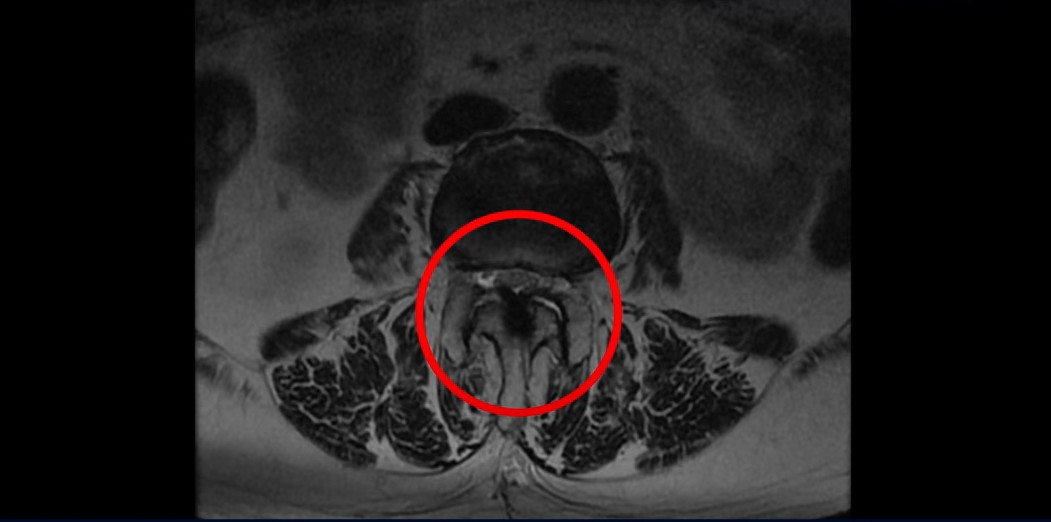

3번과 4번 마디에는 황색인대 골화증으로 인한 중심성 협착이 보입니다.

4번과 5번 마디는 전방전위증이 있고 15년 전 허리수술을 받은 적이 있어서 척추 후관절과 후궁을 제거한 흔적들이 보입니다.

또 5번 1번에는 왼쪽 신경가지가 빠져나가는 추간공 즉 신경구멍이 많이 좁아져 있습니다. 이 환자분은 허리통증과 함께 왼쪽 다리 증상이 심하셨는데 이것 때문인 것으로 보입니다.